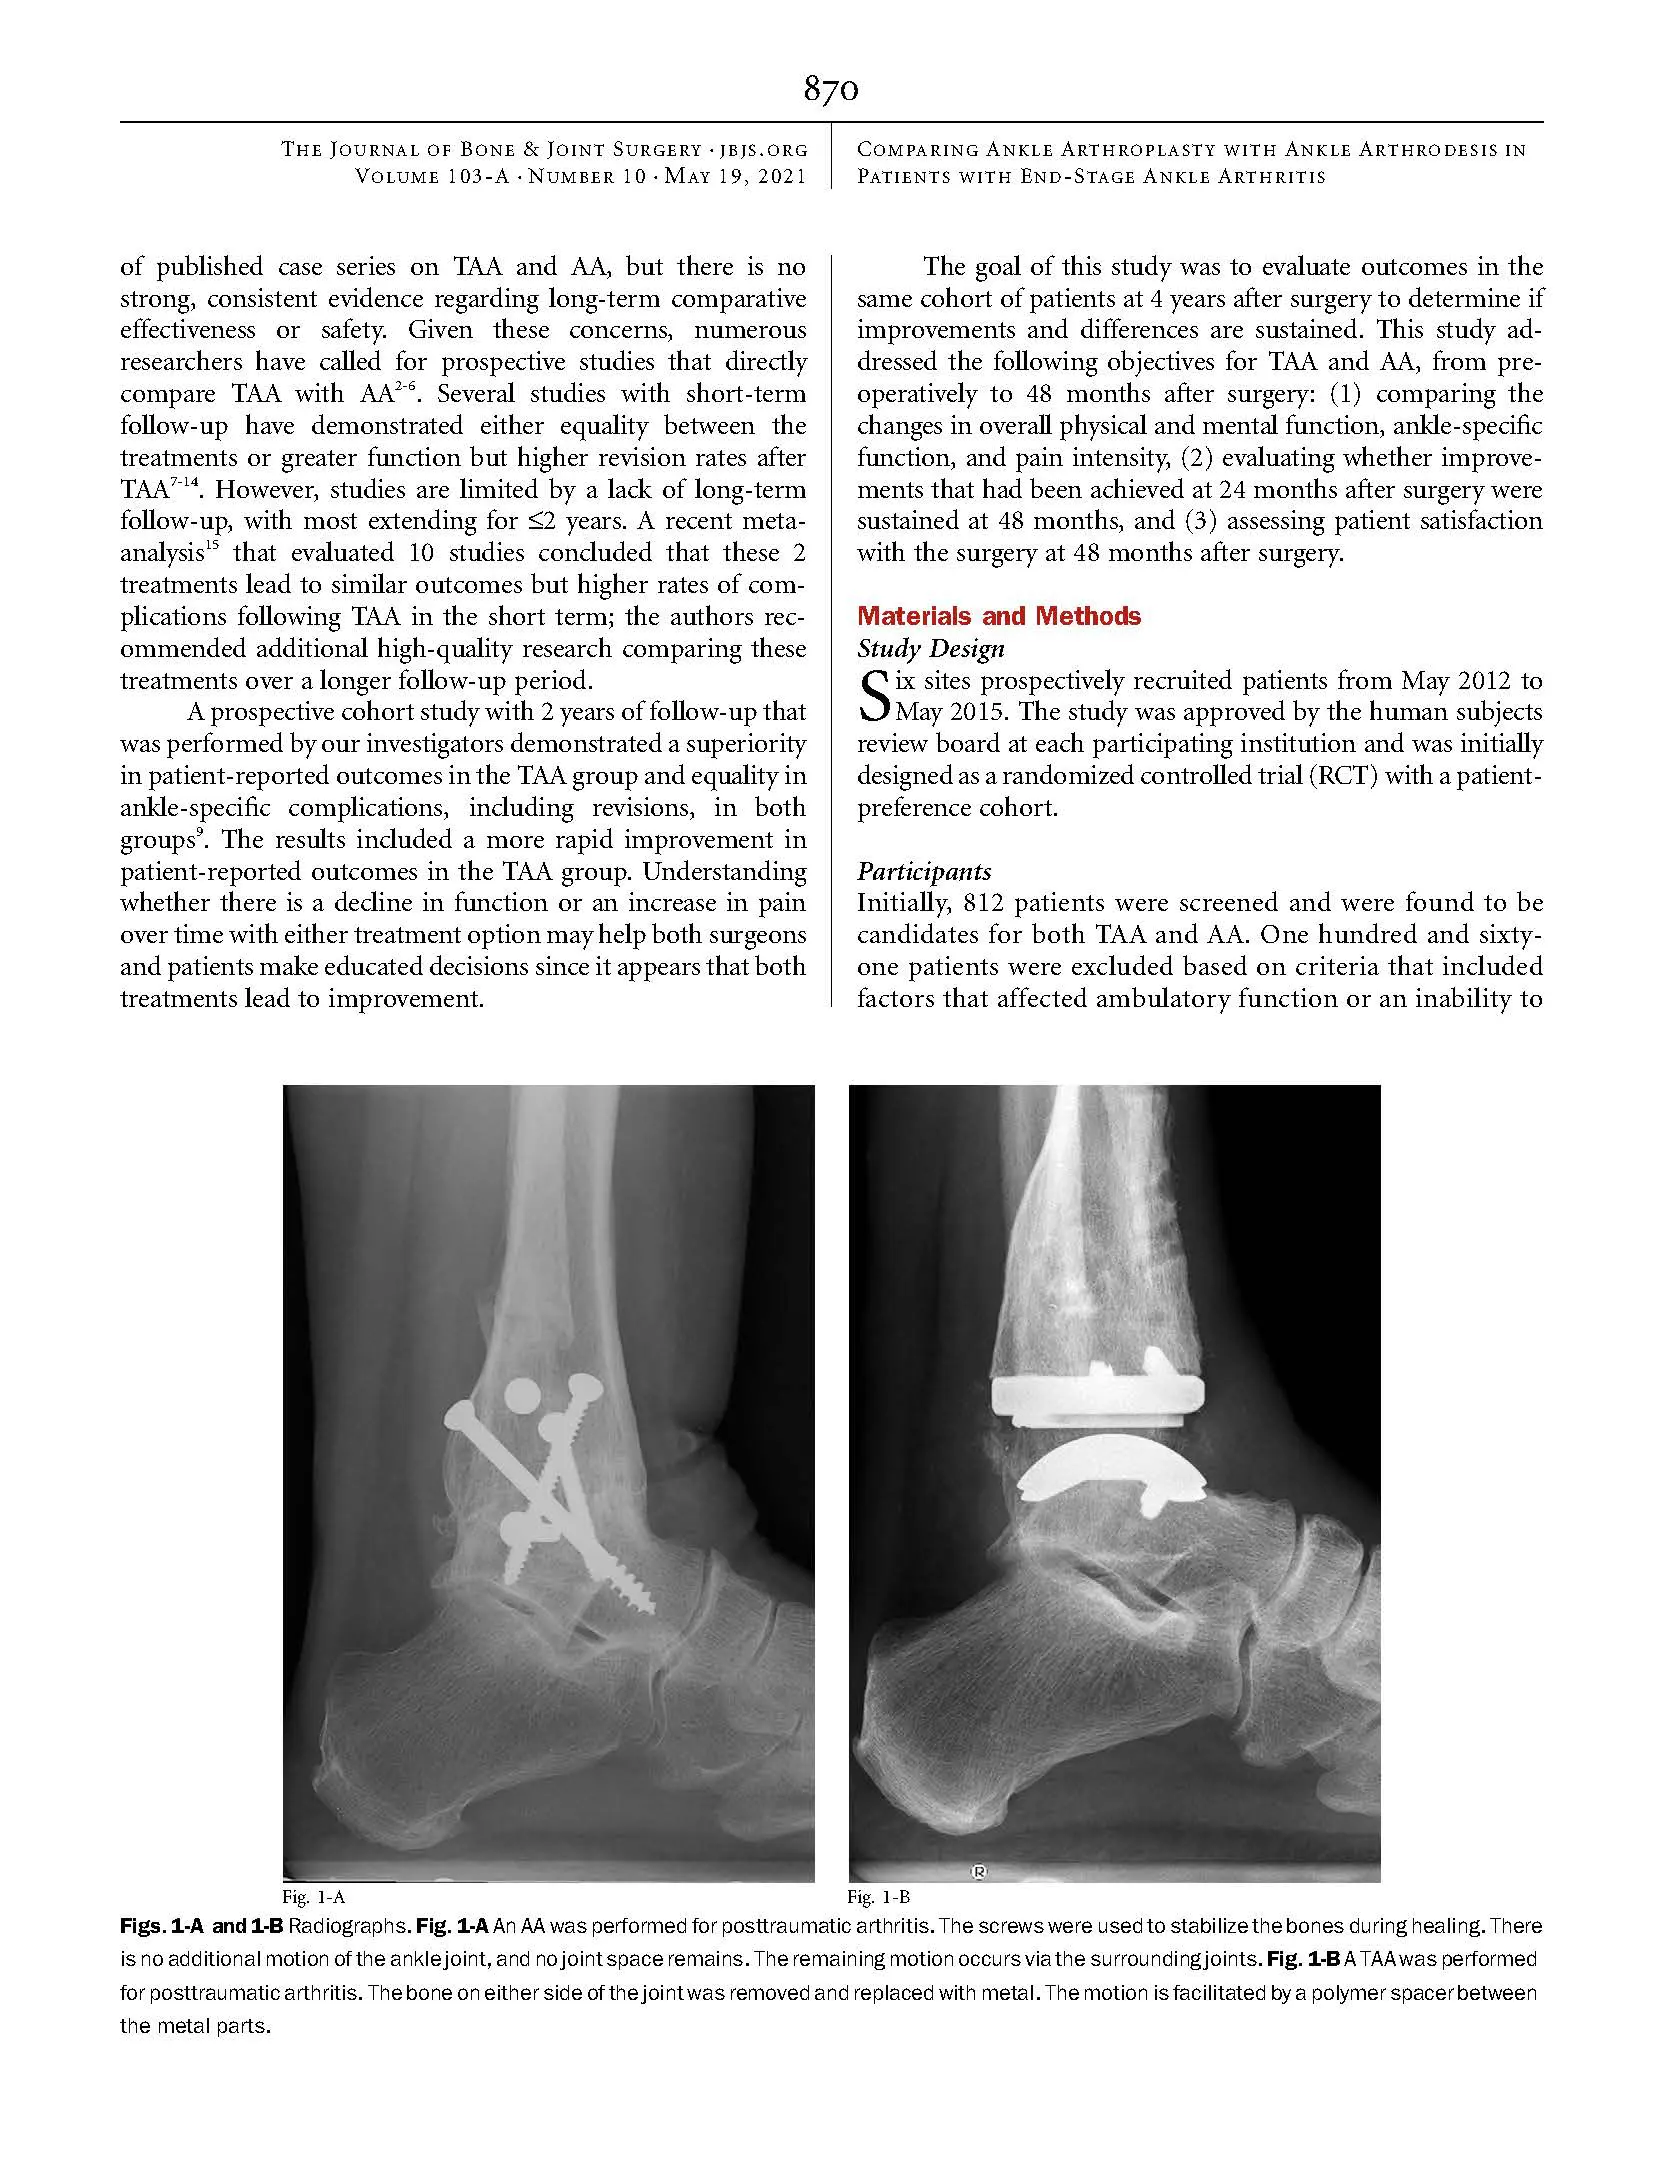

Comparing 4 Year Changes in Patient Reported.4 Page 01 Comparing 4-Year Changes in Patient-Reported Outcomes Following Ankle Arthroplasty & Arthrodesis | Amber Vance, ACNP-C, FNP orthopedic spine surgeons Comparing 4 Year Changes in Patient Reported.4 Page 02 Comparing 4-Year Changes in Patient-Reported Outcomes Following Ankle Arthroplasty & Arthrodesis | Amber Vance, ACNP-C, FNP orthopedic spine surgeons Comparing 4 Year Changes in Patient Reported.4 Page 03 Comparing 4-Year Changes in Patient-Reported Outcomes Following Ankle Arthroplasty & Arthrodesis | Amber Vance, ACNP-C, FNP orthopedic spine surgeons Comparing 4 Year Changes in Patient Reported.4 Page 04 Comparing 4-Year Changes in Patient-Reported Outcomes Following Ankle Arthroplasty & Arthrodesis | Amber Vance, ACNP-C, FNP orthopedic spine surgeons Comparing 4 Year Changes in Patient Reported.4 Page 05 Comparing 4-Year Changes in Patient-Reported Outcomes Following Ankle Arthroplasty & Arthrodesis | Amber Vance, ACNP-C, FNP orthopedic spine surgeons